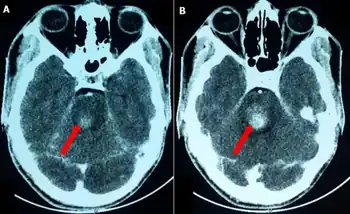

Foville's syndrome is caused by the blockage of the perforating branches of the basilar artery in the region of the brainstem known as the pons.[1] It is most frequently caused by vascular disease or tumors involving the dorsal pons.

Structures affected by the infarct are the dorsal pons(pontine tegmentum) which comprises paramedian pontine reticular formation (PPRF), nuclei of cranial nerves VI and VII, corticospinal tract, medial lemniscus, and the medial longitudinal fasciculus. There is involvement of the fifth to eighth cranial nerves, central sympathetic fibres (Horner syndrome) and horizontal gaze palsy.

The reason for Foville's syndrome is pontine infarction, however, tumors in the pons have occured as well[2]